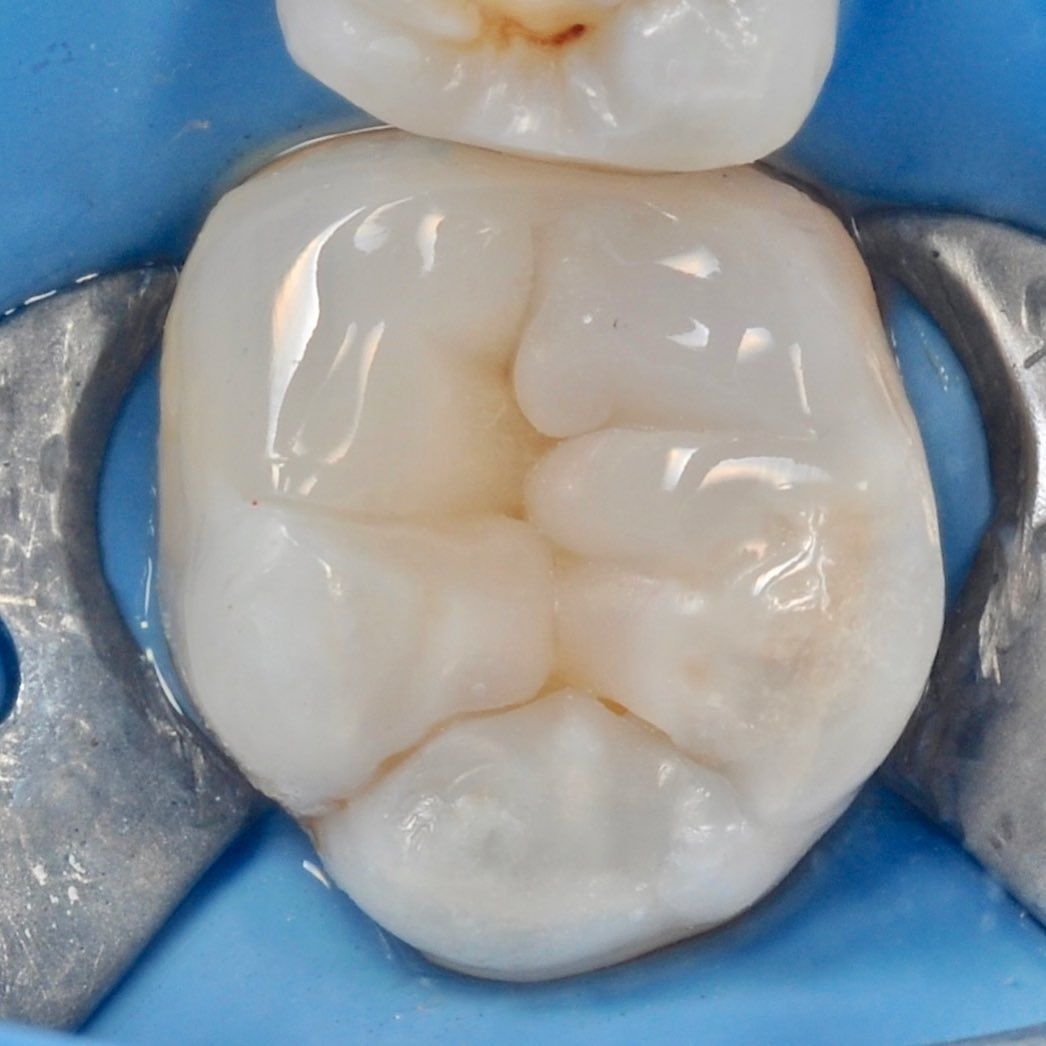

Root canal treatment

We successfully treat complex cases of canal inflammation thanks to the good equipment and experience of doctors.

careful treatment of canals

Accurate determination of the geometry of the channels and their high-quality processing